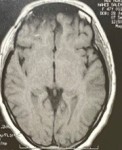

hemorrhage in the left hemisphere of the brain extending to the ventricles of the brain